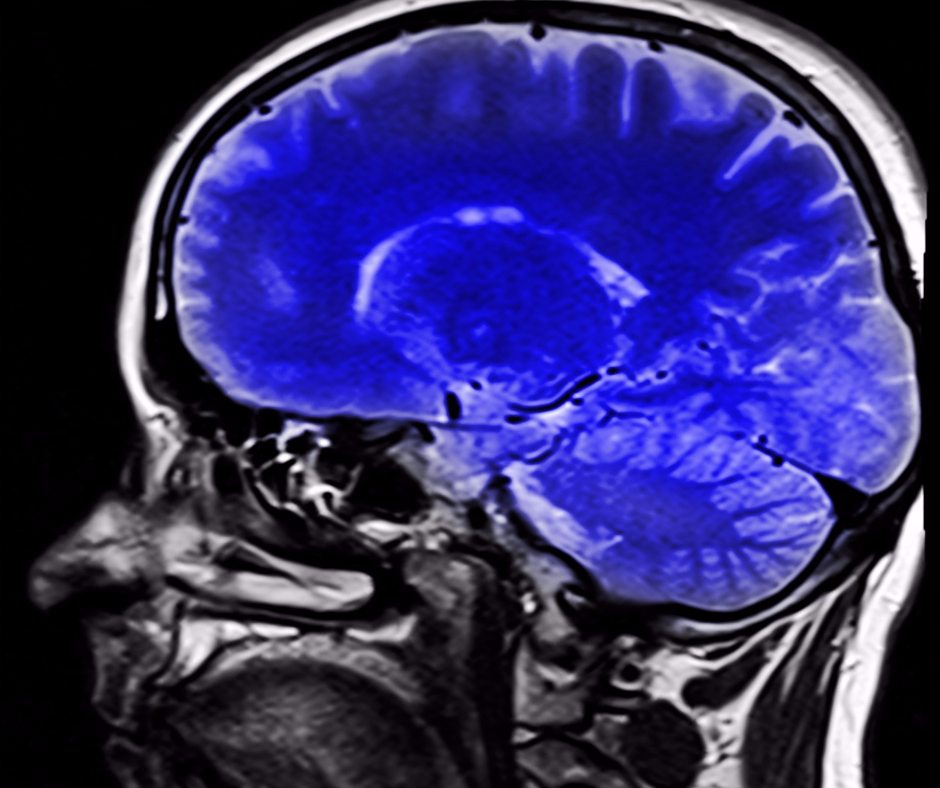

What are the most effective methods for reprogramming your brain after narcissistic abuse? The body keeps the score: There is also a physical aspect of brain damage involved—when suffering consistent emotional abuse, victims experience a shrinking of the hippocampus and a swelling of the amygdala.

Narcissistic abuse neuroscience course caring for the brain after narcissistic abuse caring for the brain after narcissistic abuse is an online course for survivors of relational trauma. Narcissistic abuse is the psychological, sexual, financial, and physical abuse of others by a narcissist. When children suffer at the hands of a narcissistic abuser, some crucial brain regions are affected, including damage to the hippocampus and amygdala.

Caring for your brain after narcissistic abuse by bree bonchay, lcsw | december 10, 2017 unfortunately, for most survivors of narcissistic abuse, ending an emotionally abusive relationship and going no contact doesn’t immediately put an end to or erase the damage left behind from the trauma of being in a toxic relationship. Children of narcissists also, like their parent(s), form brain damage from maltreatment. Through certain methods like eye movement desensitization and reprocessing therapy, or emdr, victims exhibiting signs of ptsd can regrow 6% of their hippocampus in just a few sessions.

Emdr can also calm the amygdala at the same time, allowing your brain to react more rationally to situations. And brainspotting can really help to speed up the process! Healing the brain after narcissistic abuse with dr.